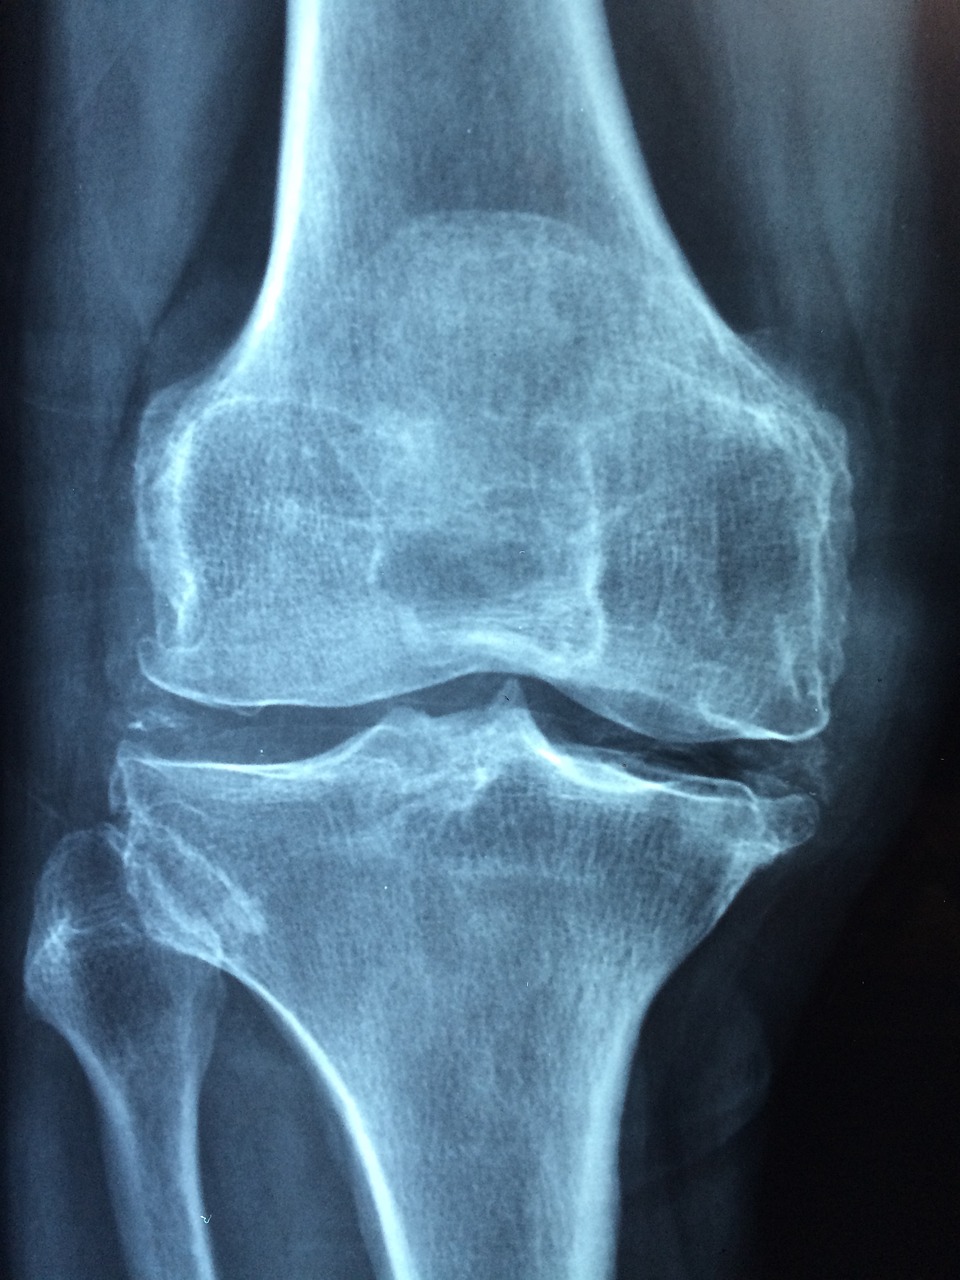

일반적으로 관절을 싸고 있는 활막에 염증이 생기면서 관절이 붓고 통증이 발생한다. 이러한 염증이 지속되면 염증성 활막 조직들이 점차 자라나면서 뼈와 연골을 파고들어 관절의 모양이 변형되고 관절의 움직임이 장애가 발생한다.

류마티스 관절염의 진단에는 혈액검사, X-ray 검사 등을 보조적으로 사용한다. 문진과 이학적 검사가 가장 중요한 진단의 단서가 된다. 따라서 혈액 검사에 아무리 류마티스 인자가 나온다고 하더라도 증상이 없으면 류마티스 관절염으로 진단하지 않는다. ( 이학적 검사 - 청진, 촉진(만져봄), 타진(두드려 몸) 등등 의사의 손으로 검사하는 것)